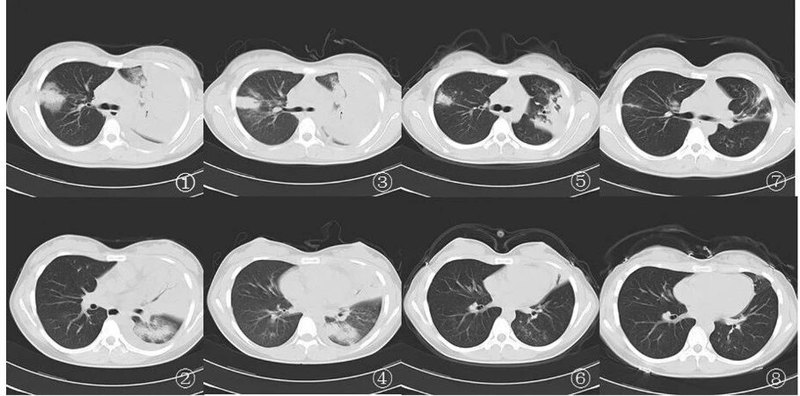

廣大群眾需要認識的嗜肺軍團菌